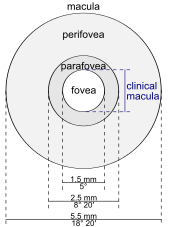

The macula or macula lutea (from Latin macula, "spot" + lutea, "yellow") is an oval-shaped pigmented area near the center of the retina of the human eye. It has a diameter of around 5.5 mm (0.22 in). The macula is subdivided into the umbo, foveola, foveal avascular zone (FAZ), fovea, parafovea, and perifovea areas.[1] After death or enucleation (removal of the eye) the macula appears yellow, a color that is not visible in the living eye except when viewed with light from which red has been filtered.[2] The anatomical macula at 5.5 mm (0.22 in) is much larger than the clinical macula which, at 1.5 mm (0.059 in), corresponds to the anatomical fovea.[3][4][5] The clinical macula is seen when viewed from the pupil, as in ophthalmoscopy or retinal photography. The anatomical macula is defined histologically in terms of having two or more layers of ganglion cells.[6] The umbo is the center of the foveola which in turn is located at the centre of the fovea.

Regions

- Fovea - 1.55 mm (0.061 in)

- Foveal Avascular Zone (FAZ) - 0.5 mm (0.020 in)

- Foveola - 0.35 mm (0.014 in)

- Umbo - 0.15 mm (0.0059 in)